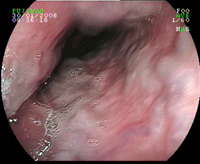

Endobrachyoesophage